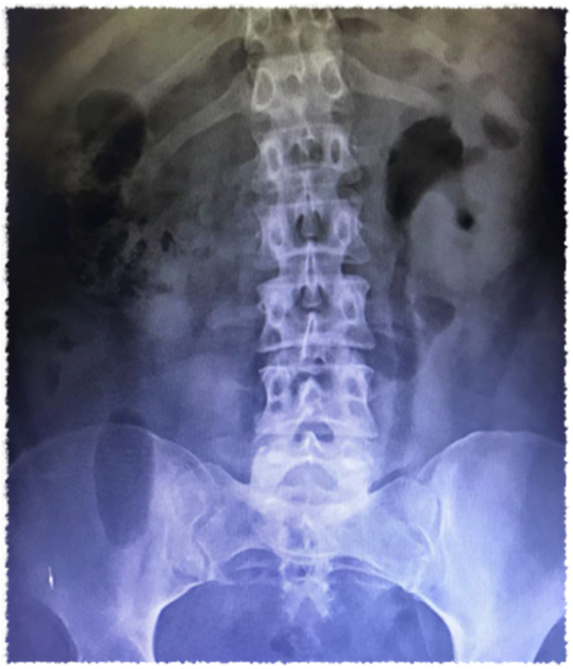

El diagnóstico se confirma con las pruebas radiológicas. En la radiografía de abdomen se puede hallar gas tisular distribuido en el parénquima, que se evidencia como sombras gaseosas sobre el riñón comprometido (Imagen 1).2

Imagen 1 a) Placa simple de abdomen en donde se observa claramente la presencia de gas en ambos riñones, extendiéndose hacia uréter.

Este hallazgo muchas veces se confunde con gas intestinal. Una colección de gas en forma de medialuna sobre el polo superior del riñón es más específica.1,2 A medida que la infección avanza, el gas se extiende al espacio perinéfrico y al retroperitoneo.